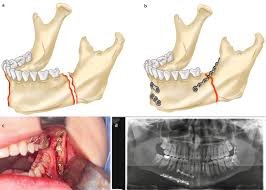

Jaw Fracture Treatment

Specialized care for jaw fractures and trauma. Our advanced treatment techniques ensure proper healing and restoration of jaw function.